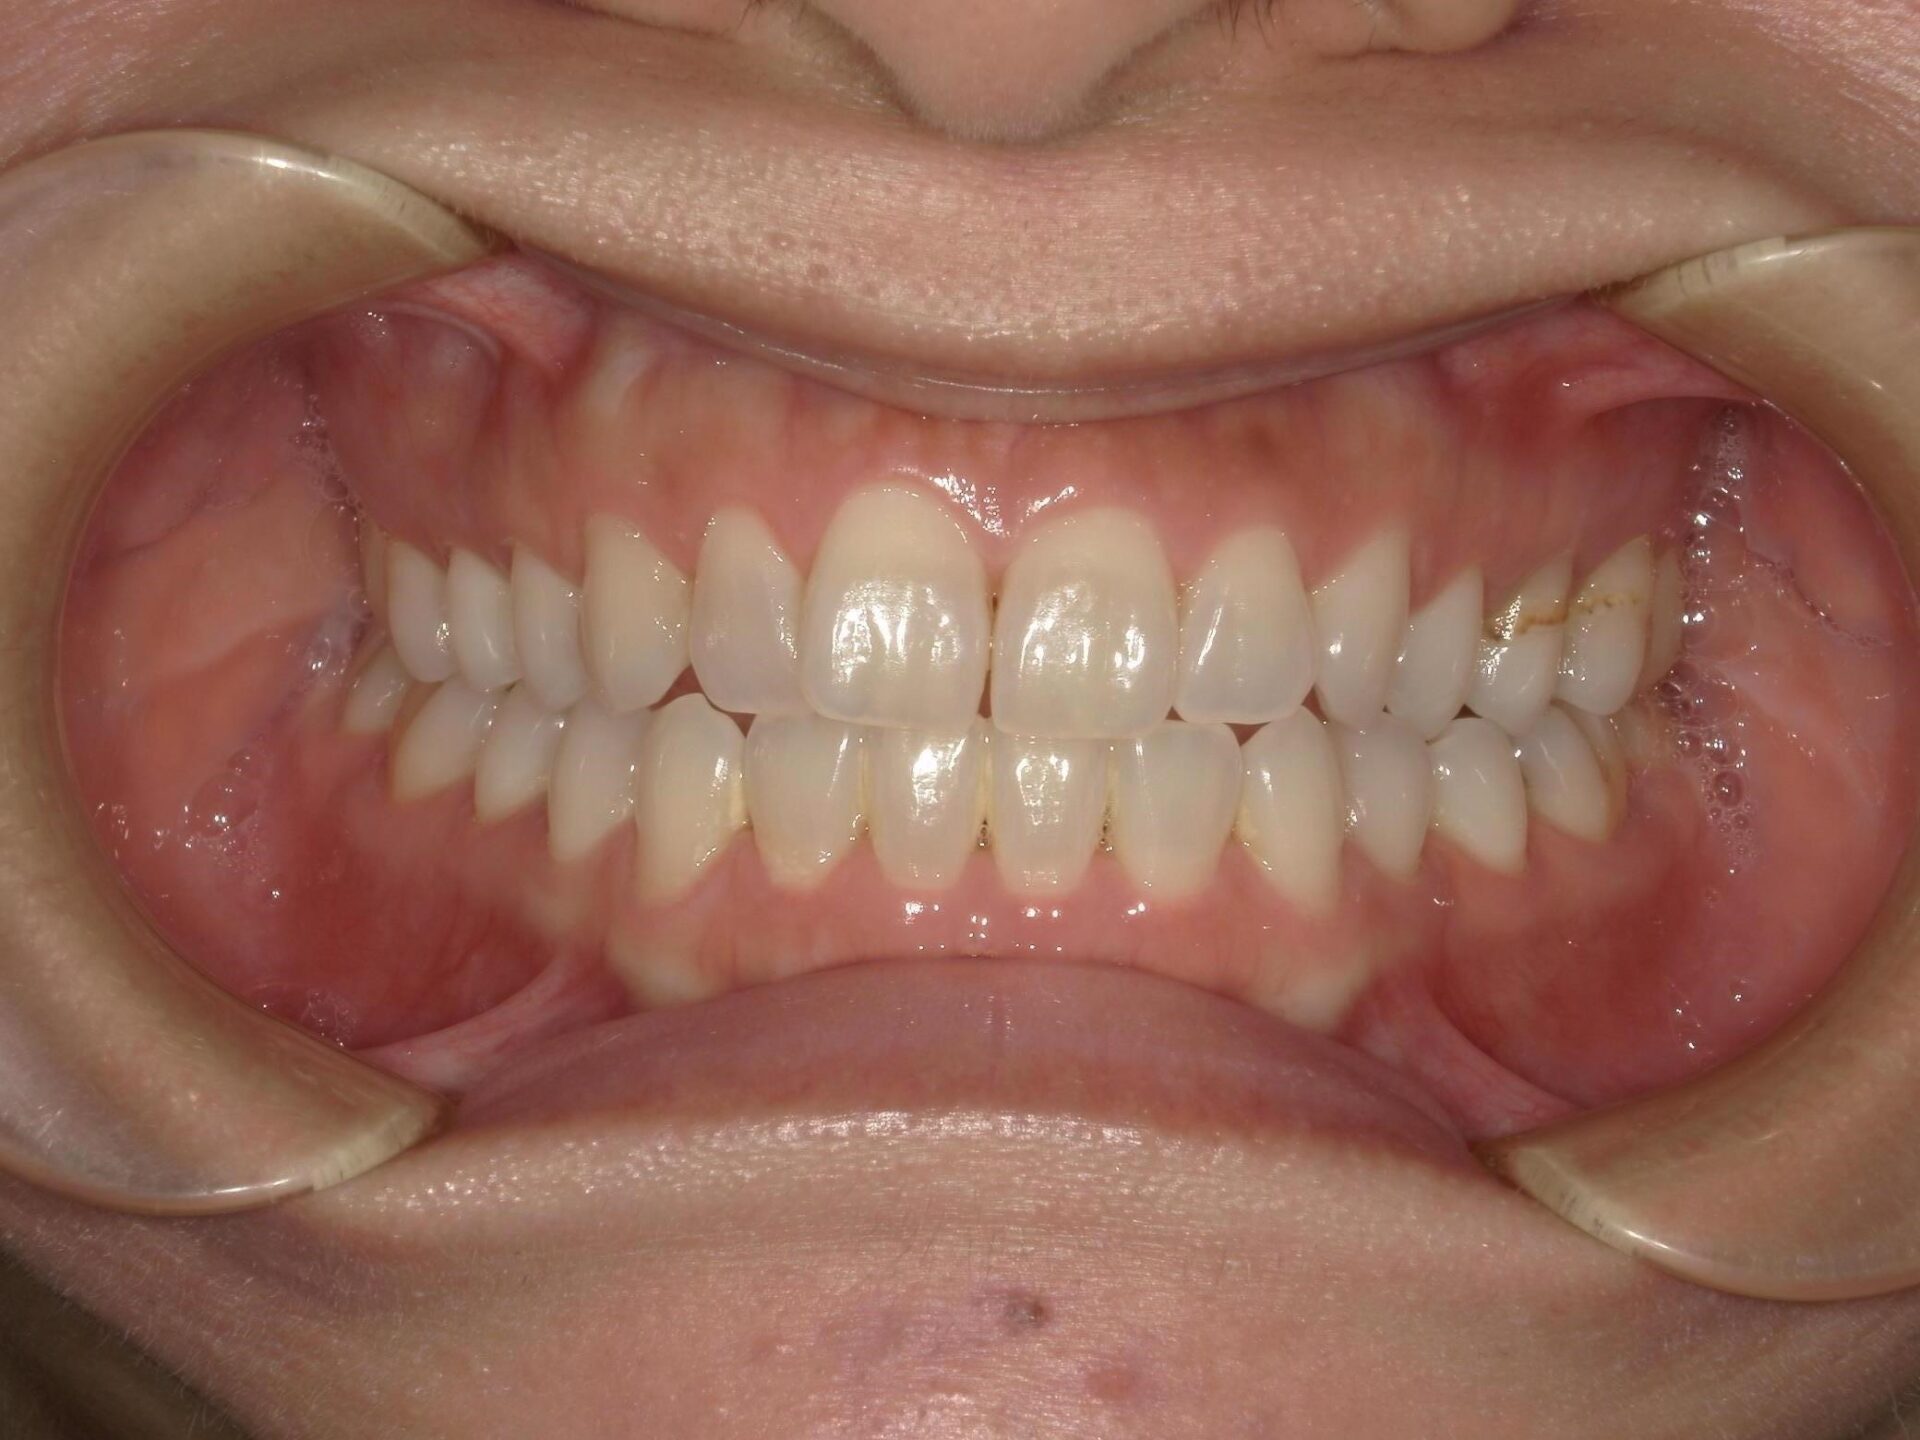

20代、女性、ワイヤー

| 施術内容 | 主訴:口ゴボが気になる。 詳細:ワイヤー矯正での歯並び改善 口元がかなり変化し、とても満足された症例です。 |

| 治療期間 | 16ヶ月(3/24現在 治療終了) |

| リスク・副作用 | ■リスク・副作用 ・治療の初期段階では、痛みや不快感が生じやすくなりますが、一週間前後で慣れます。 ・歯の動き方には個人差があるため、予想された治療期間より延長する場合があります。 |

| 費用 | ワイヤー矯正 60万円(税込660,000円) |